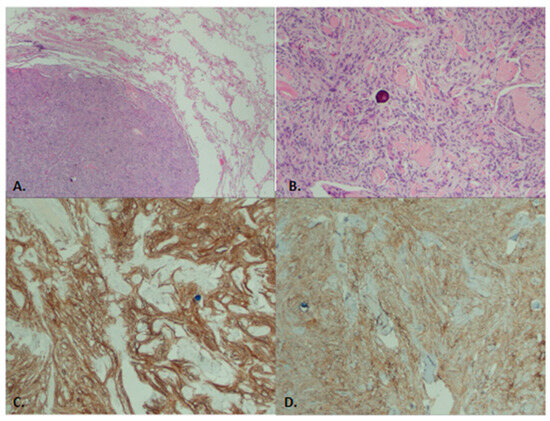

A Rare Case of Primary Pulmonary Meningioma

by Calista Sha, Leo Li, Fernanda Mitchell, Frank Breuer, Riona Park and Paul C. Lee

J. Clin. Med. 2025, 14(8), 2688; https://doi.org/10.3390/jcm14082688 - 15 Apr 2025

Background: Primary pulmonary meningioma (PPM) is an uncommon tumor originating in the lung. Although predominantly benign, there are instances of aggressive tumors exhibiting malignant features. Due to their rarity, our understanding of PPMs is primarily gleaned from case reports or small case [...] Read more.

Background: Primary pulmonary meningioma (PPM) is an uncommon tumor originating in the lung. Although predominantly benign, there are instances of aggressive tumors exhibiting malignant features. Due to their rarity, our understanding of PPMs is primarily gleaned from case reports or small case series. Methods: This report details the case of an 84-year-old female presenting with an incidental, well-circumscribed, enlarging nodule (1.4 × 1.3 × 0.9 cm) in the left upper lobe (LUL). Initial imaging found it to be highly suspicious of lung cancer. Results: Upon surgical resection, pathological analysis confirmed the tumor’s characteristics to be consistent with a benign PPM. Postoperative recovery was uneventful and there is no evidence of recurrence. Conclusions: Our report aims to contribute to the expanding body of knowledge concerning incidental PPMs by documenting our clinical encounter with this patient. Full article

(This article belongs to the Section Respiratory Medicine)

Show Figures

Figure 1